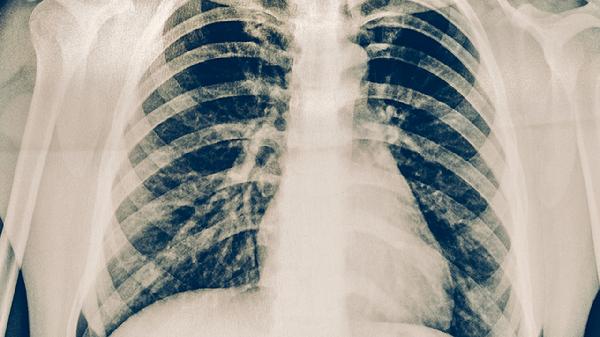

使用靶向药物前必须进行基因检测明确突变类型,治疗期间定期复查CT评估疗效。出现严重不良反应如间质性肺病或重度肝损伤需立即停药。联合传统化疗或免疫治疗时需调整给药方案。保持均衡饮食补充优质蛋白,避免葡萄柚等影响药物代谢的食物。严格遵医嘱控制给药剂量和周期,不可自行增减药量。